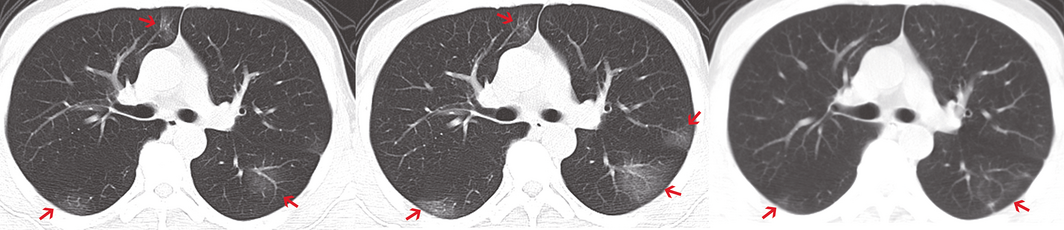

For 29 of the 31 patients, pneumonia was evident on chest CT imaging, including 20 with bilateral involvement (Supporting Information); for two patients, no abnormalities were evident on chest CT at any point. The typical radiological changes were bilateral or bilobular ground glass opacity that usually progressed within one week (Box 2).

Box 2 – Chest computed tomography (CT): typical findings, including bilateral involvement and ground glass opacities (arrows) that resolved within one week